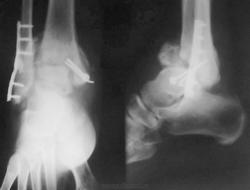

Пациентке 50 лет, в марте 2011 получила бытовую травму, при поступлению в одну из ЦРБ Нижегородской области был диагносцирован трехлодыжечный перелом, наружный подвывих стопы (рентгенограммы 1). Поскольку боковая рентгенограмма сделана с ротацией, никто не обратил внимания на передний отдел метаэпифиза б/берцовой кости. Пациентке налажено скелетное вытяжение (рентгенограммы 2,3), на боковом снимке видно повреждение переднего отдела метаэпифиза, но внимание на это не обращается, выполняется стандартный остеосинтез наружной и внутренней лодыжек (рентгенгограммы 4), опять же ни о кого не возникает никаких вопросов, а именно: почему дисконгруэнтна суставная щель, стопа в переднем подвывихе и в эквинусе. В августе пациентка приходит на контроль, и уже отчетливо виден дефект переднего отдела метаэпифиза б/берцовой кости, смещение костного фрагмента метаэпифиза кпереди и передний вывих стопы, но никаких мероприятий не проводится. Вчера, 9.02 пациентка все же доходит до нашего института, и мы видим такую картину (рентгенограммы 5,6): дефект переднего края дистального метаэпифиза б/берцовой кости, костный фрагмент смещен кпереди, некротизирован (фактически это секвестр), стопа в положении переднего вывиха, разрыв дистального межберцового синдесмоза, нестабильность металлоконструкций в б/берцовой кости (отчетливо видна резорбция), асептический некроз блока таранной кости. Прогноз неблагоприятен: артродезирование г/стопоного сустава, вопрос только в выборе метода, аппаратный артродез, либо ретроградный интрамедуллярный.